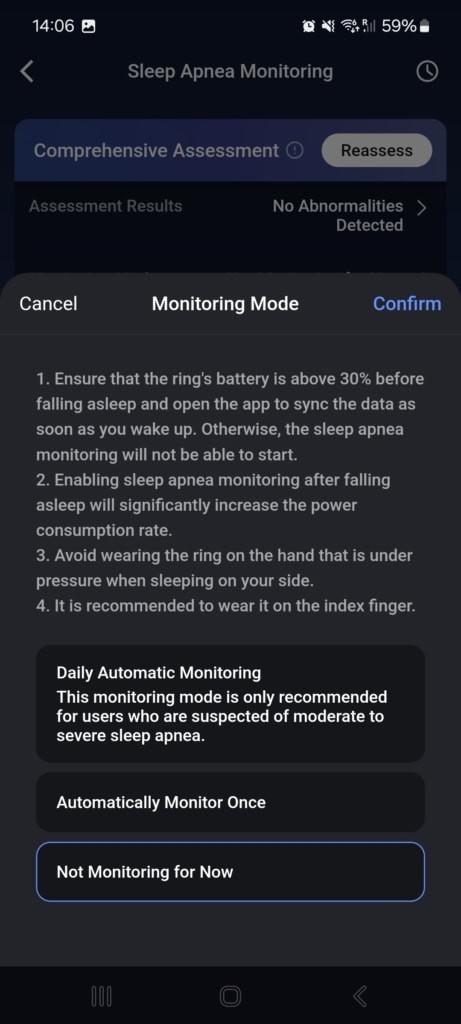

Aby uzyskać kompleksową analizę, smart ring potrzebuje trzech nocy, podczas których wykrywa nieprawidłowości oddechowe. Na podstawie ustalonego wskaźnika dochodzi do zmiany trybu monitorowania. Użytkownicy z niskim lub zerowym wskaźnikiem nie wymagają dalszego monitorowania. Osoby w strefie lekkiego bezdechu mogą zmienić tryb na jedno automatyczne pomiarowanie w celu weryfikacji wyniku. W przypadku wysokiego wskaźnika i podejrzenia średniego do ciężkiego bezdechu dostępne jest codzienne automatyczne monitorowanie.